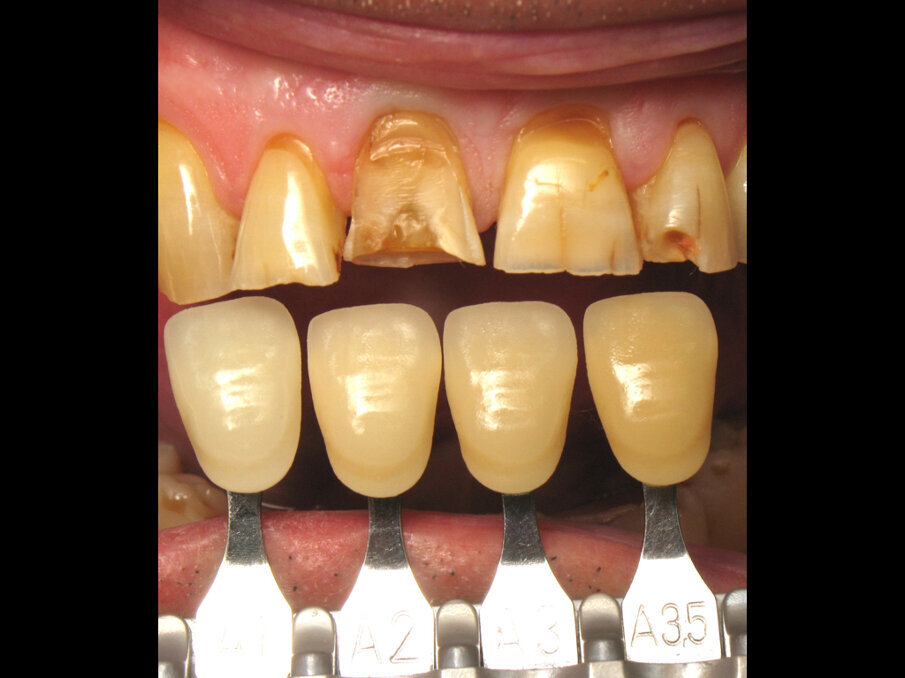

Taken 1 hour earlier, Figure 10 shows a real patchwork of tooth shades. There was translucency of the incisal edge, cervical saturation, cracks, missing restorations and a complex coronary fracture of tooth #11. All these elements caused the teeth to react by building reactionary dentine over time, and that was the source of the several shade differences.

Fig. 10: Pre-op tooth shade.